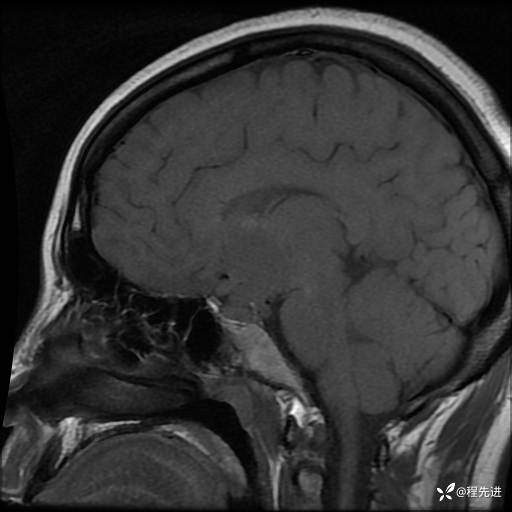

T2: